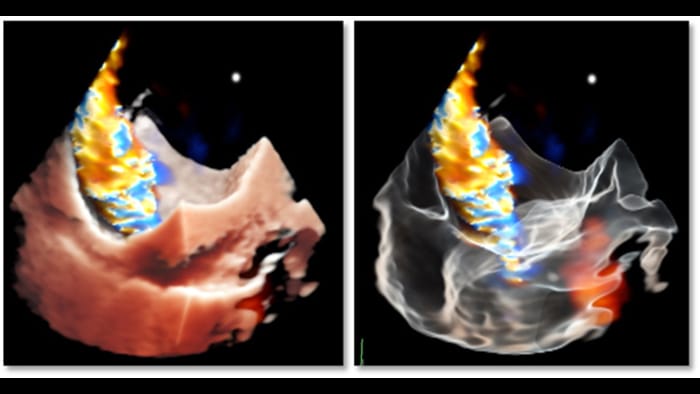

Wyczerpujące dane kliniczne dzięki rekonstrukcji TrueVue Color i GlassVue

Fotorealistyczna rekonstrukcja Cardiac TrueVue z funkcją wyrównywania obrazów MultiVue